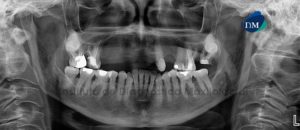

Paciente de sexo masculino de 45 años se acerca al Instituto de Diagnóstico Maxilofacial para evaluación integral por motivos de colocación de implantes. A la